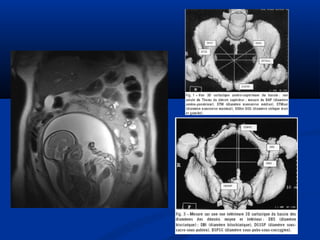

Xaùc ñònh vò tríxöông söôøn treân CT